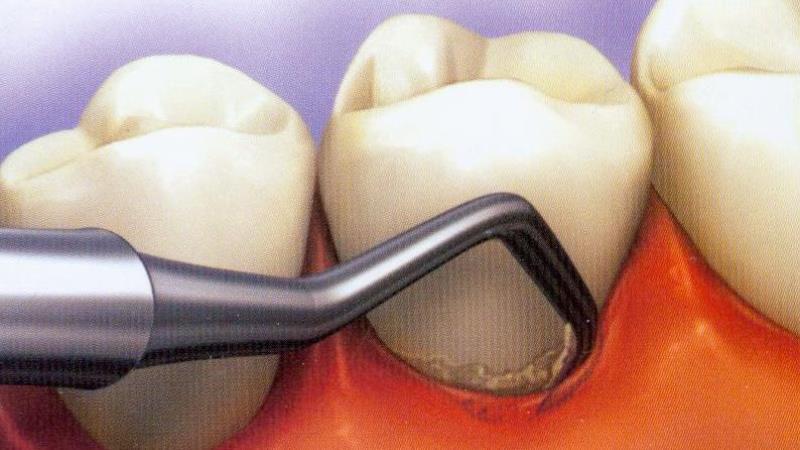

Как проходит процедура? Сначала медсестра вводит местную проводниковую анестезию, после чего врач начинает чистку карманов с использованием ручных или ультразвуковых инструментов. Специалист тщательно удаляет мягкие и твердые отложения под деснами, исследуя каждый карман и удаляя из него заместительную ткань и патологические массы. Очищенные области промываются изотоническим раствором на основе хлорида натрия. Затем врач полирует корни зубов.